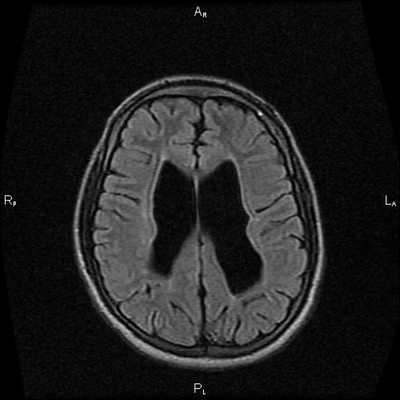

Магнитно-резонансная томография

МРТ позволяет легко установить диагноз. При отсутствии изображений с насыщением жировой ткани в качестве полезного подспорья можно использовать артефакт химического сдвига. Сигнальные характеристики соответствуют жировой ткани:

- T1: высокая интенсивность МР сигнала

- T2: высокая интенсивность МР сигнала

- T1 (с парамагнетиками): отсутствие усиления сигнала

- последовательности с насыщением жировой ткани: низкая интенсивность МР сигнала

При МРТ головного мозга установлено: МРТ признаки хронической недостаточности мозгового кровообращения; выраженная открытая внутренняя гидроцефалия, свидетельствующая о признаках атрофических изменений в головном мозге.